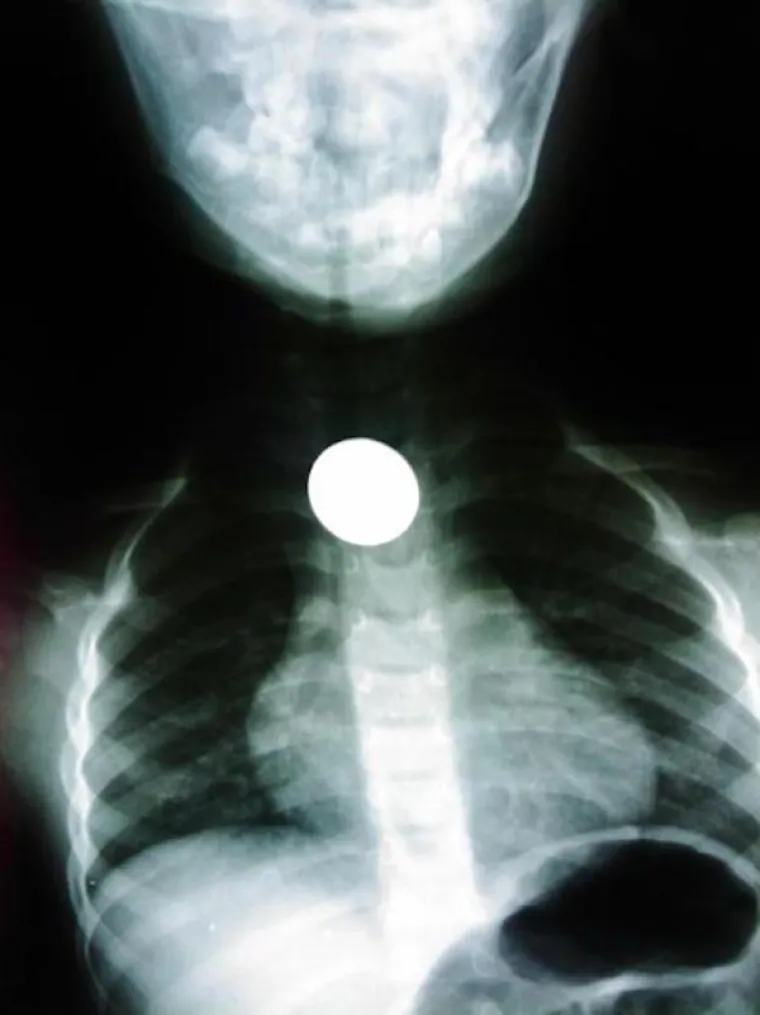

LJUDI SU ČAROBNO SPREMIŠTE, U NJIH STANE BAŠ SVE: Nevjerojatne snimke pokazuju što su sve uspjeli ugurati u sebe